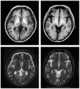

Manganese inhalation